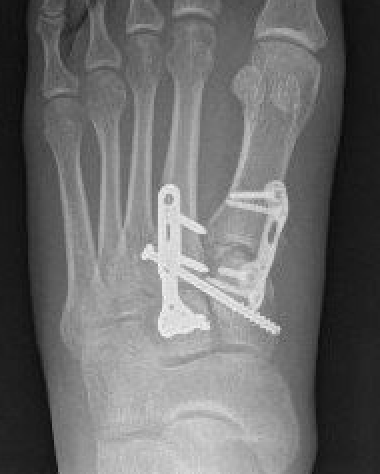

Screw fixation

AP view

- 1st metatarsal to medial cuneiform - screw

- 2nd metatarsal to intermediate cuneiform - screw

- medial cuneiform to base of second metatarsal - screw

+/- medial cuneiform to intermediate cuneiform - screw

Bridge plate to 1st TMT and second TMT with Lisfranc screw